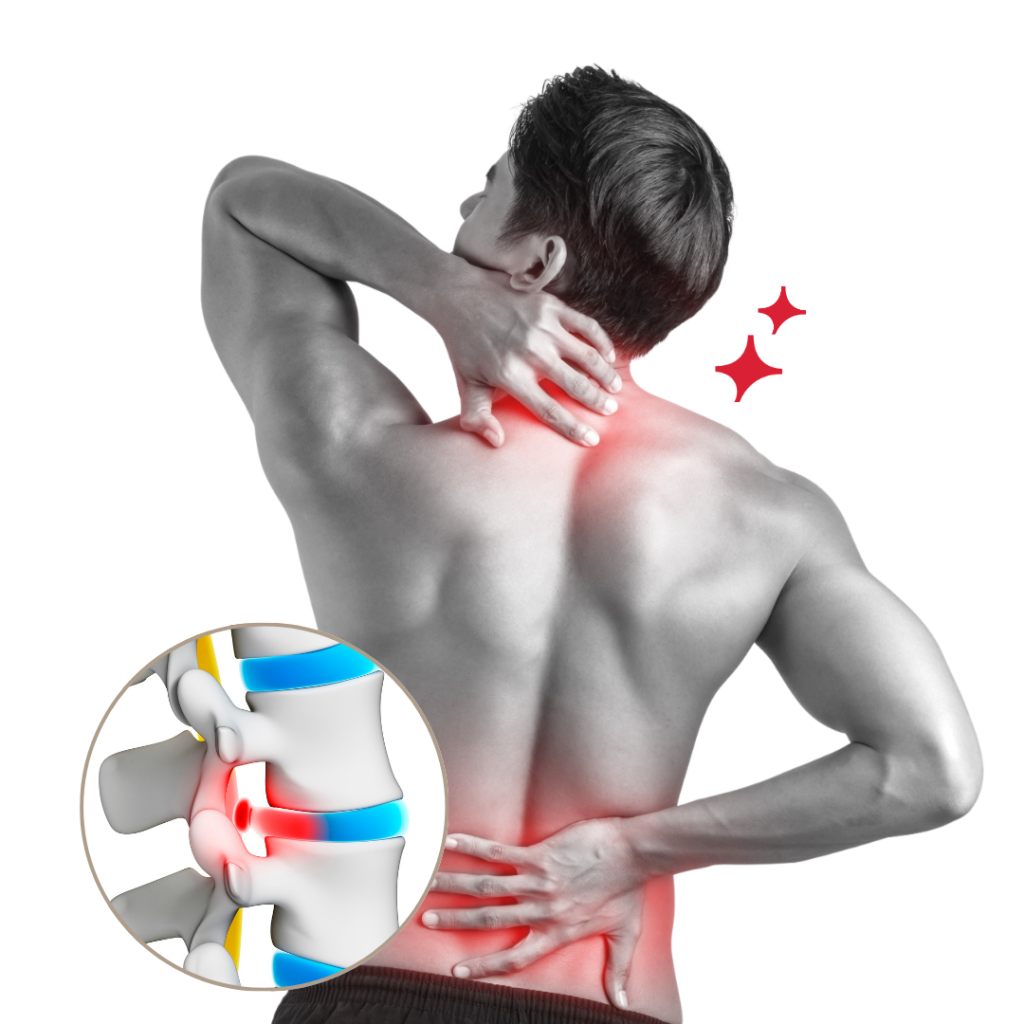

Are You Suffering from Ongoing Pain and Discomfort?

If you identify with any of these symptoms:

- Stiff and achy muscles

- Injuries related to work or exercise

- Neck pain due to prolonged sitting

- Back pain from lifting heavy objects

- Feeling weaker than you'd like to be

We’re here to assist in alleviating your pain and discomfort using proven physiotherapy methods. Many of our patients report noticeable relief after just 3 to 5 sessions. Reach out to us to learn about special offer for new patients.